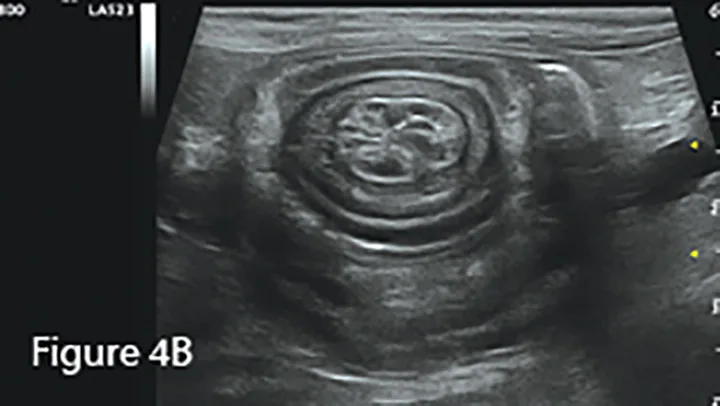

Invagination of 1 portion of the GI tract (intussusceptum) into the lumen of another (intussuscipiens); this is often referred to as the target sign when seen in the transverse plane because of the multiple layers of adjacent intestinal walls.